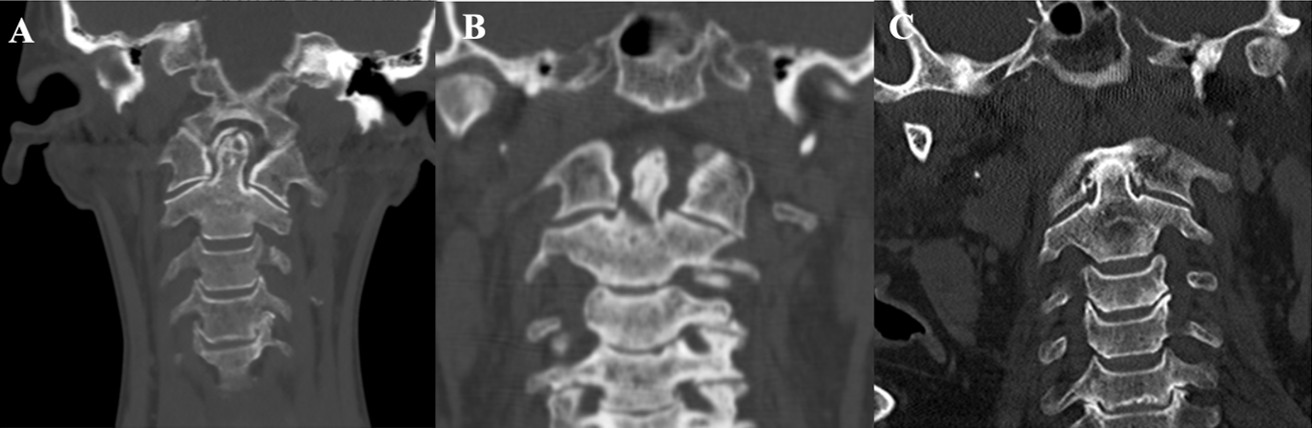

Yöntemler: Bu retrospektif çalışmaya, 2018–2023 yılları arasında üçüncü basamak bir beyin cerrahisi merkezinde tedavi edilen 65 odontoid kırıklı hasta dahil edildi. Kırıklar, Anderson ve D’Alonzo sınıflamasına göre değerlendirildi; Tip II kırıklar ayrıca Grauer sınıflaması kullanılarak alt gruplara ayrıldı. Yaş, travma mekanizması, kırık alt tipi, tedavi yöntemi ve radyolojik sonuçlar gibi klinik veriler analiz edildi.

Bulgular: Hastaların ortalama yaşı 61,9 yıl olup, olguların %56,9’u ≥65 yaşındaydı. En sık travma mekanizması, özellikle yaşlı hastalarda görülen düşük enerjili kendi seviyesinden düşmelerdi (%50,7). Anderson ve D’Alonzo sınıflamasına göre en sık Tip II kırıklar (%53,8) saptanırken, bunu Tip III kırıklar (%44,6) izledi. Tip II kırıkların %82,5’i Tip IIB alt grubundaydı. Hastaların %33,8’ine cerrahi tedavi uygulanmış olup, en sık tercih edilen yöntem anterior odontoid vida fiksasyonuydu. Hastaların %66,2’si ise konservatif olarak tedavi edildi. Bilgisayarlı tomografi ile yapılan takiplerde (n=42) füzyon oranı %76,1 olarak bulundu. Cerrahi tedavi uygulanan hastalarda füzyon oranı %84,2 iken, konservatif tedavi edilenlerde %69,5 idi. Füzyon oranı, 65 yaş altı hastalarda (%81,8) yaşlı hastalara (%70) kıyasla daha yüksek bulundu.